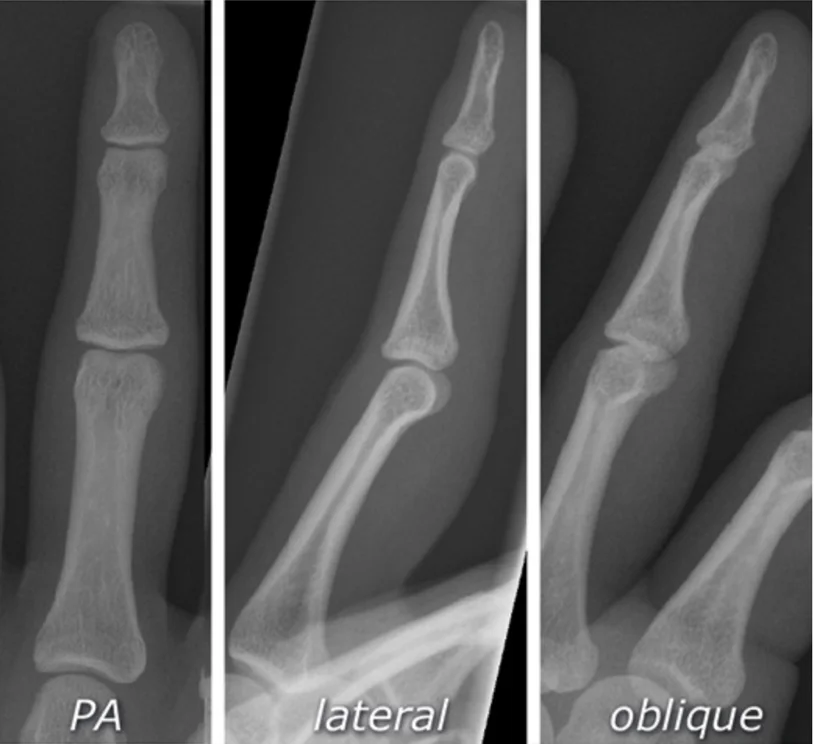

Important to have two views

- Site: Shaft tibia â lowerâŻ1/3

- Type: Simple

- Fracture line: Transverse

- Displacements: Lateral & posterior shift; minimal medial & anterior tilt

- Special issues: Joint above not visualized